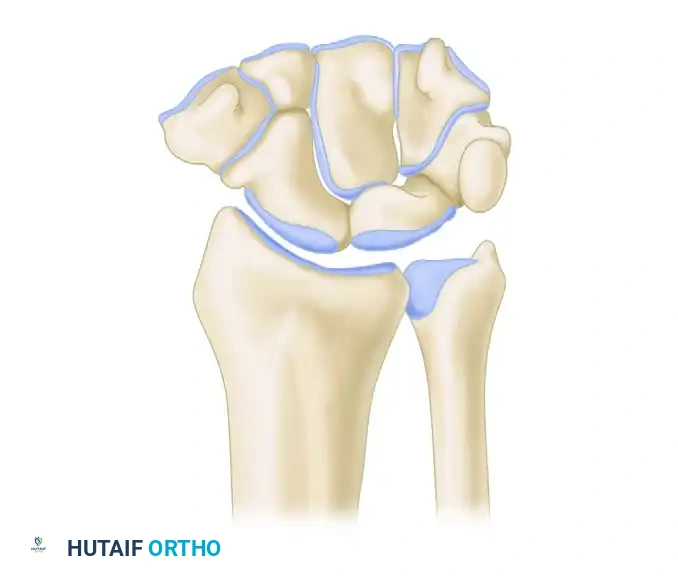

Radiocarpal and Midcarpal Articulations

The radiocarpal joint is formed by the articulation of the distal radius with the proximal carpal row (scaphoid and lunate) via distinct concave facets. The triquetrum articulates with the triangular fibrocartilage complex (TFCC) rather than directly with the distal ulna.

The midcarpal joint is formed by the distal concave articular surfaces of the proximal carpal row articulating with the distal carpal row (trapezium, trapezoid, capitate, hamate).